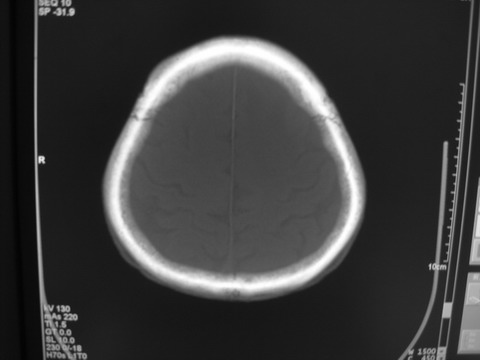

患者 男 69岁 头晕头痛不适

多发病灶,指状水肿,首先诊断转移瘤。

多个结节并周围大面积水肿区,多考虑多发性脑转移瘤

小病灶、大水肿,病灶多发,首先考虑多发转移瘤;建议查原发灶。

额顶叶多发小病灶、大水肿,首先考虑多发转移瘤;建议查原发灶

脑内多发病灶,小病灶,大水肿。

典型转移性肿瘤。

应进一步检查,查找原发病灶。

结果 : 该患者结肠癌病史5年 考虑脑转移